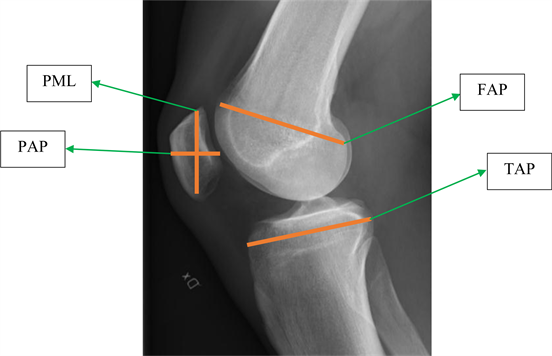

Totally, 14 dimensions measured and DICOM program used for measuring (dimensions demonstrated by mm) (Figure 1, Figure 2).

Figure 2. Tibial and patellar dimensions’ X-ray (Femur anterior-posterior (FAP), tibia anterior-posterior (TAP), Patella medial lateral PML, Patella anterior-posterior (PAP)).